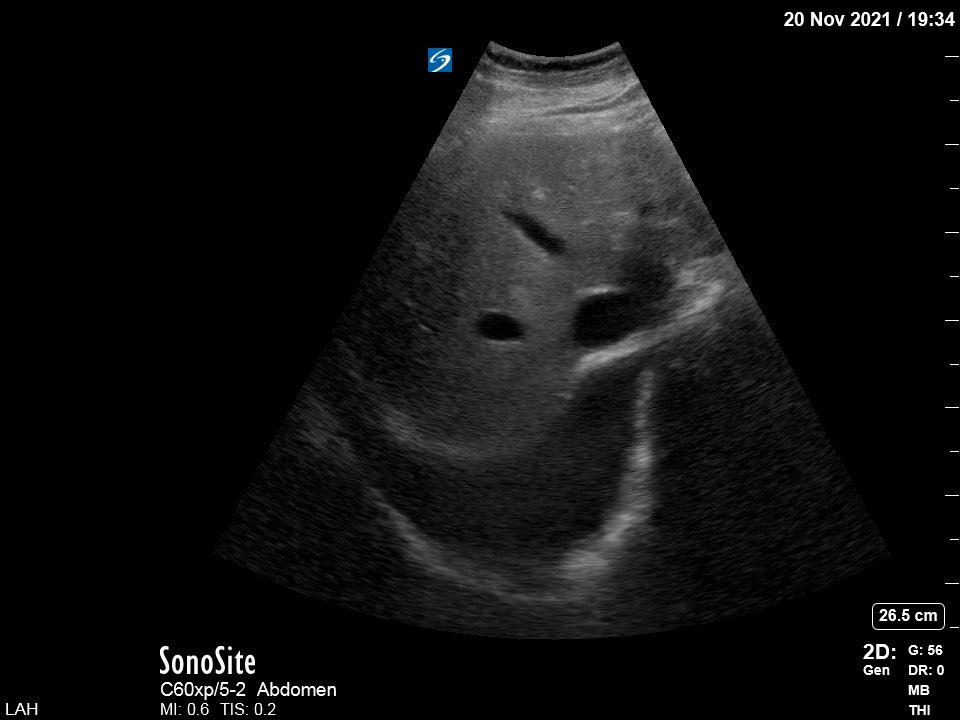

My next step was to look at the venous side. Pt tachypneic and in A fib (I will skip the poor HV and renal vein Doppler clips). This was the interesting transverse IVC view (at increased depth to look also at the R pleural space):

☝️Full IVC and large R effusion. The admission CXR was read as "no evidence of pleural effusion". This was the chest CT for comparison:

Back to the venous side and VEXUS. The IVC was large (almost 3 cm) but there were no "supportive" HV or renal vein Doppler images